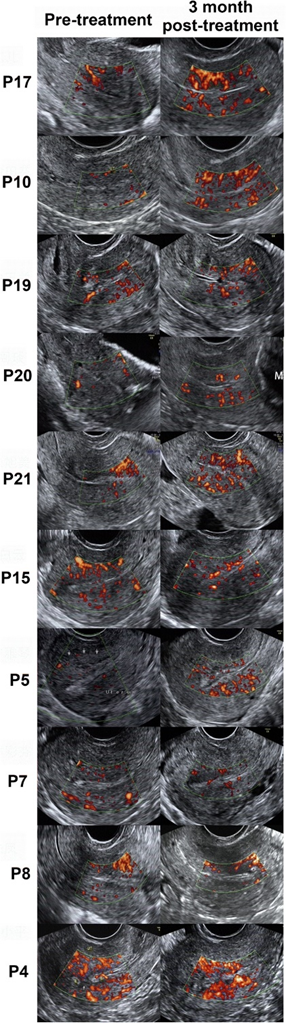

研究结果表明:脐带间充质干细胞可能是宫腔粘连潜在的治疗方法。该研究纳入26例复发性宫腔粘连导致不孕症患者,将1×10^7个脐带间充质干细胞(UC-MSCs)负载到胶原支架上,在宫腔粘连松解后移植到患者宫腔内,而后进行3个月的随访,评估患者子宫内膜厚度、宫腔粘连评分及子宫内膜增殖分化相关分子的变化。

随访结果发现[3],UC-MSCs移植后未发生与治疗相关的严重不良事件;术后3个月,患者平均子宫内膜厚度较治疗前明显增加,宫腔粘连评分较前降低。此外,组织学研究表明治疗后子宫内膜的增殖、分化和新生血管均有改善。到30个月随访期结束时,26例患者中有10例怀孕,其中8例已经分娩,无明显出生缺陷和胎盘并发症。

图为患者治疗前后超声对比 图片来自文献[3]